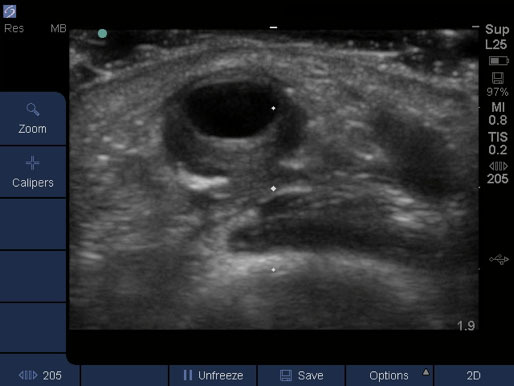

Dialysis Vessel Wall Injury Image